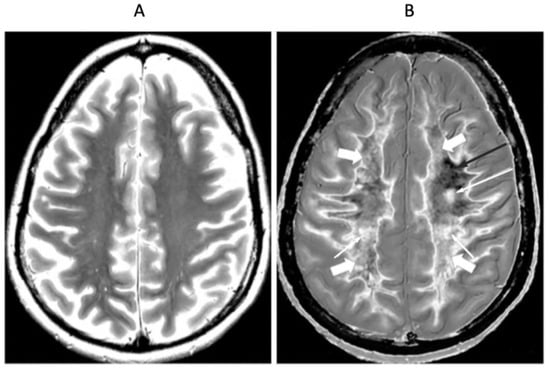

Figure 8 shows positionally matched supraventricular T2-FLAIR (Figure 8A) and narrow mD dSIR (Figure 8B) images in a patient with MS during a relapse. A single lesion is seen on the T2-FLAIR image, and this is also seen on the dSIR image (long white arrows). An additional six lesions are only seen on the dSIR image (short white arrows). Many of the lesions on the dSIR image have high signal boundaries (rims). In addition, there are bilateral symmetrical widespread relatively uniform increases in signal in white matter, with some sparing of more peripheral white matter. These are features of a high grade (4–5) (maximum grade 5) whiteout sign [6]. This differs from the normal dark appearance of white matter seen on the narrow mD dSIR image in Figure 6B. No evidence of a whiteout sign is seen on the T2-FLAIR image.

Figure 8.

Thirty-two-year-old female patient with MS undergoing a relapse. T2-FLAIR (A) and synthetic narrow mD dSIR (B) images. On the T2-FLAIR image, one lesion is seen (long arrow). The surrounding white matter appears normal. On the dSIR image (B), the lesion shown on the T2-FLAIR image is seen (long arrow) as well as six other lesions (short arrows). Most of the white matter in (B) is high signal corresponding to a high grade 5 (out of 5) whiteout sign [7]. This is in contradistinction to the appearance of the peripheral white matter in the patient with MS in remission shown in Figure 6B. where the peripheral white matter is low signal.